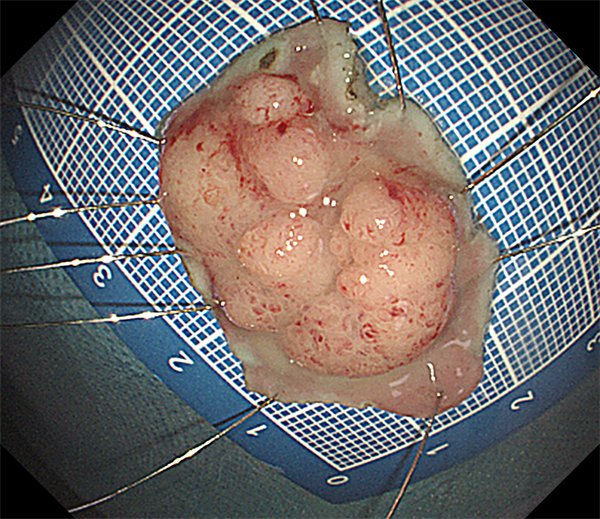

患者周某,男60岁,体检行肠镜发现直肠肿物,行肠镜下直肠黏膜下剥离术(ESD),术后病理:绒毛状管状腺瘤,局灶呈高级别上皮内瘤变。